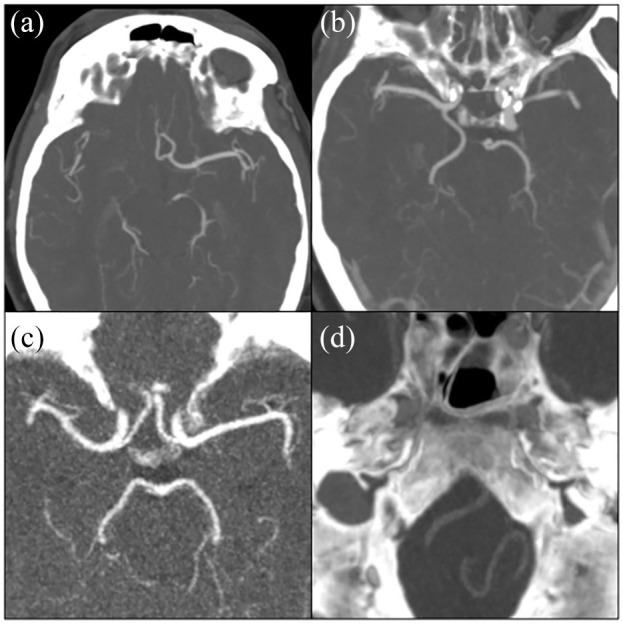

Methods: Between December 2005 and October 2010, 1126 patients (mean age: 62.3 (SD: ±14.0) years, 48.0% female) were recruited, 59.9% of whom had ischemic stroke and 40.1% a transient ischemic attack (TIA). Within the routine diagnostic work-up for stroke, patients underwent cranial computed tomography (CT) angiography. These images enabled a detailed visualization of intracranial arteries, which allowed for the assessment of the anatomical configuration of the cerebral arteries, the anterior and posterior communicating arteries, the internal carotids, and the vertebrobasilar arteries. In addition, these images facilitated the identification of intracranial arterial calcifications, the defining feature of intracranial arteriosclerosis. Binomial logistic regression models adjusting for age, sex, and ethnicity were constructed to assess associations between intracranial artery variations and presence of intracranial arterial calcifications.